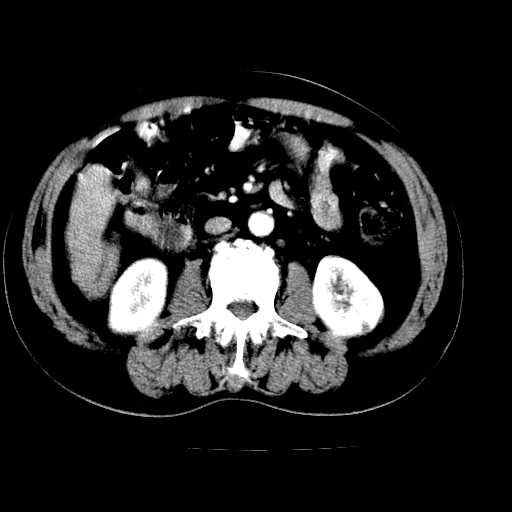

男,66岁,上腹部不适、黄染一周。彩超示:肝左叶占位,肝内胆管扩张,胆总管扩张,胆总管占位?

肝左叶不规则软组织肿块影,边缘不规整邻近肝实质受累分界不清;肝内胆管(左叶)明显扩张成“软藤状”,诊断:肝左叶胆管细胞癌。

左叶胆管细胞癌累及胆总管,门脉左支受侵,慢性胆囊炎胆结石,左肾小囊肿

肝左叶不规则软组织肿块影,边缘不规整邻近肝实质受累分界不清;肝内胆管(左叶)明显扩张成“软藤状”,诊断:肝左叶胆管细胞癌。胆囊钙乳症。